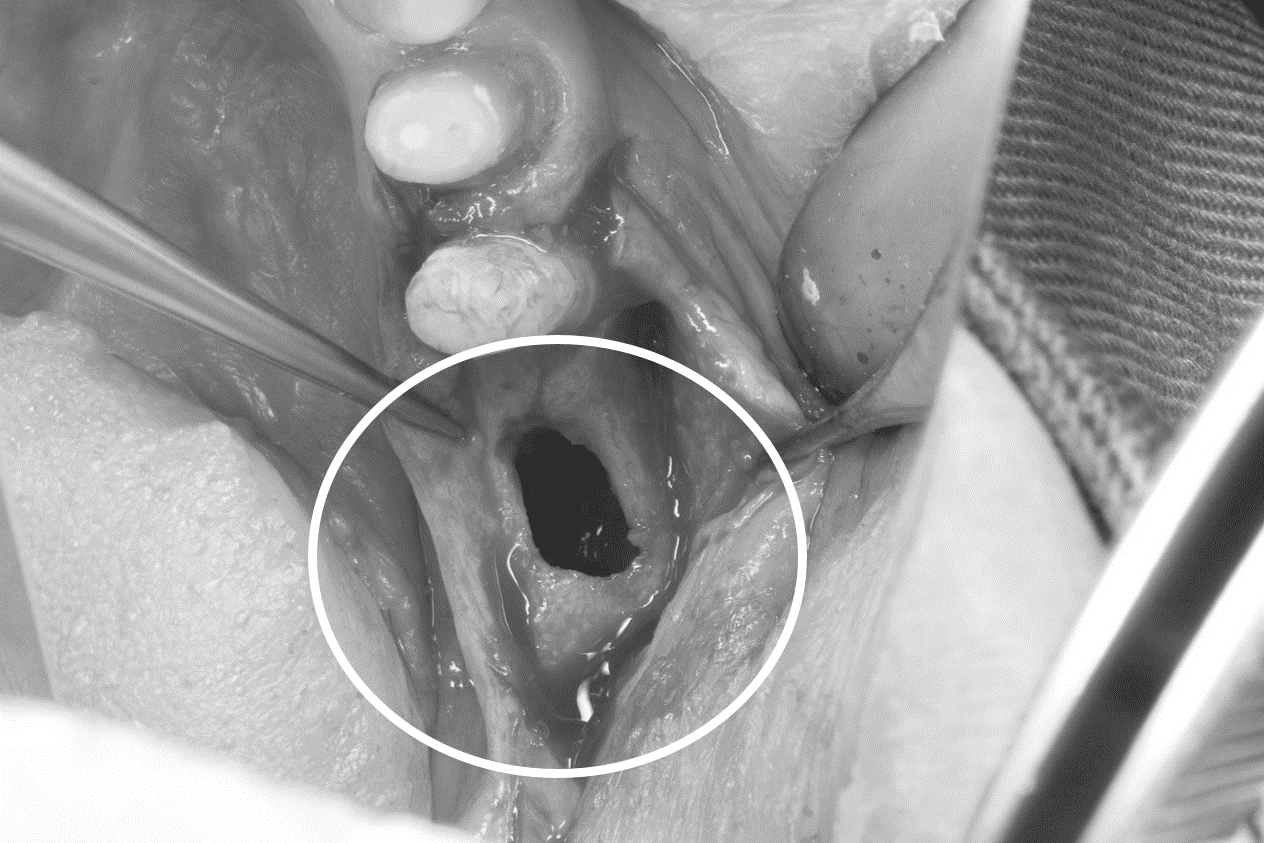

除去した時の写真

できる限り外側の健康な骨は温存しているのですが、中は広範囲に腐骨化していたため、壺状に大きく欠損しています。